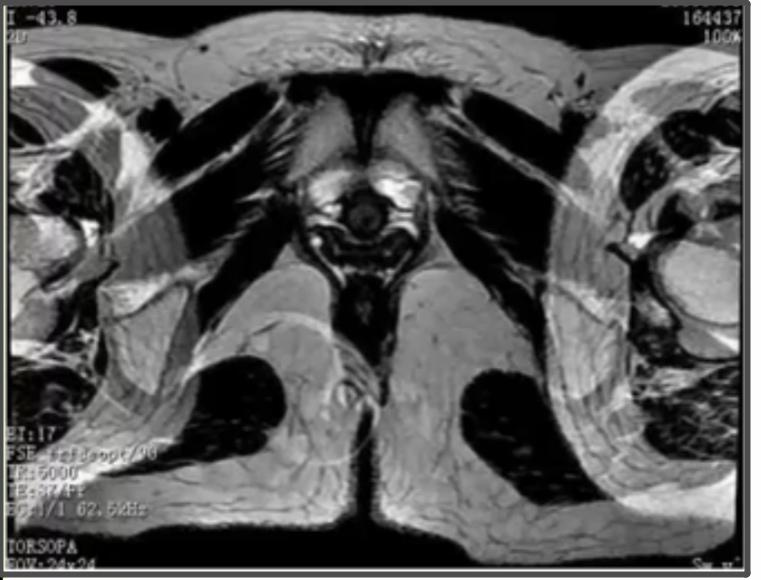

在脊柱磁共振扫描中,相位编码应该设置在上下方向,频率编码在前后方向,流动补偿技术施加在层面选择方向。

【当相位编码为上下方向时会产生化学位移伪影,压脂时此伪影消失】